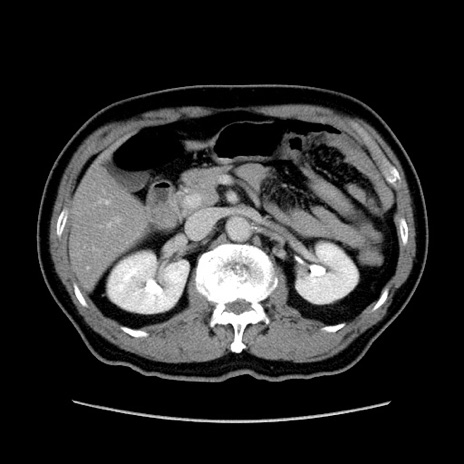

症例34(横断像)

【症例】60歳代 男性

【主訴】右鼠径部膨隆

【現病歴】1年程前より右鼠径部膨隆あり。自己にて還納可能だったため放置していた。3時間前より右鼠径部の脱出を認め、還納困難となり受診。

【既往歴】高血圧

【身体所見】右鼠径部に小児頭大の膨隆あり。弾性硬であり、用手還納は困難。左鼠径部にも膨隆を認める。脱出はなし。